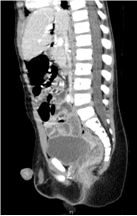

Penetrating Rectal Trauma: Laparoscopic Management without Fecal Diversion

Drahos A*, Nolan HR, Bozeman A